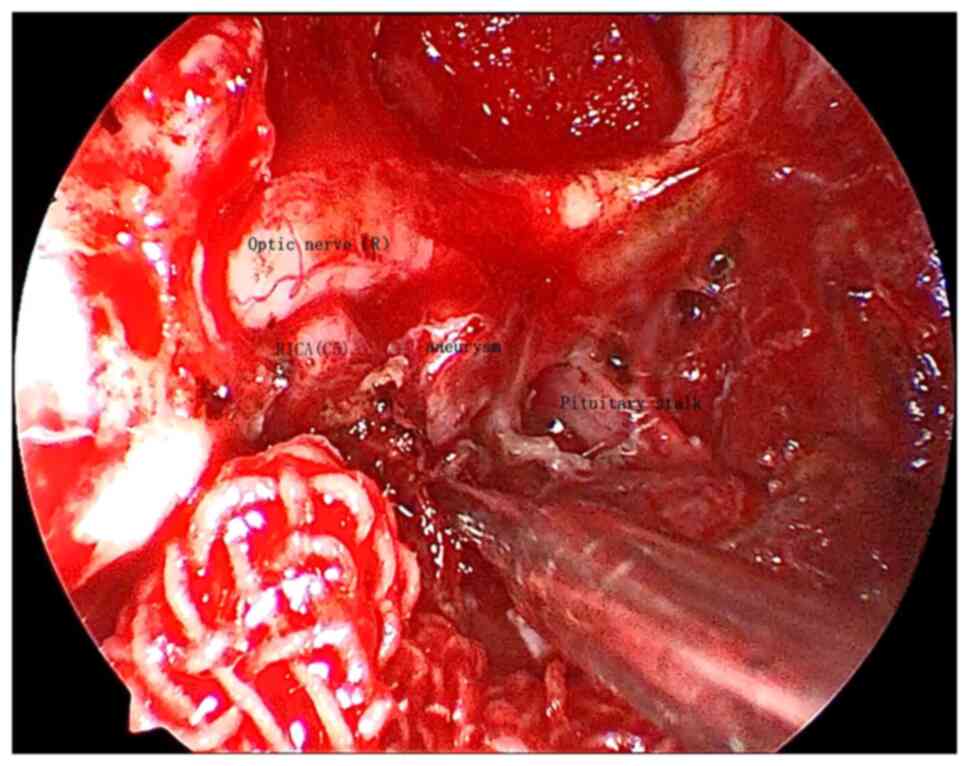

Craniopharyngioma resection and aneurysm clipping performed simultaneously by pure endoscopic endonasal approach: A case report and literature review

Craniopharyngioma is one of the most challenging issues for neurosurgeons as a brain tumor. Among the approaches of neurosurgery, in comparison to craniotomy, the endoscopic endonasal approach (EEA) has risen in popularity over the last two decades; unruptured intracranial aneurysms are relatively commonly found in the general population. The EEA as a new paradigm in the treatment of aneurysm has been reported to successfully clip dozens of cases of intracranial aneurysm. However, when reviewing the domestic and foreign literature, it appeared that cases of craniopharyngioma complicated with intracranial aneurysm purely treated by EEA have not been reported so far. In the present study, the published literature regarding endoscopic endonasal surgery for craniopharyngioma and intracranial aneurysms was reviewed, accompanied with a case of craniopharyngioma complicated with intracranial aneurysm, both of which were simultaneously treated by EEA.